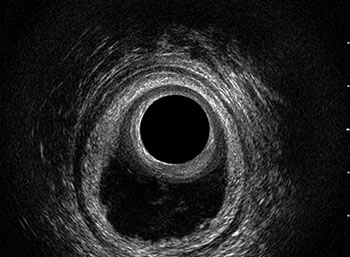

L’ecografia transanale è un esame diagnostico per immagini che consiste nell’introduzione di un trasduttore ad ultrasuoni. Le immagini qualitativamente migliori del canale anale sono ottenute usando un trasduttore rotante, montato in un manipolo rigido, che fornisce un’immagine a 360°. Con le apparecchiature più moderne è anche possibile ottenere immagini tridimensionali.

L’ecografia transanale permette di distinguere la sottomucosa che riveste il canale anale, lo sfintere anale interno, e lo sfintere anale esterno.